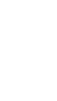

Con aparatitos como este ayudamos a que la mandíbula crezca en armonía,

los dientes tengan espacio y ... ¡adiós problemas grandes en el futuro.